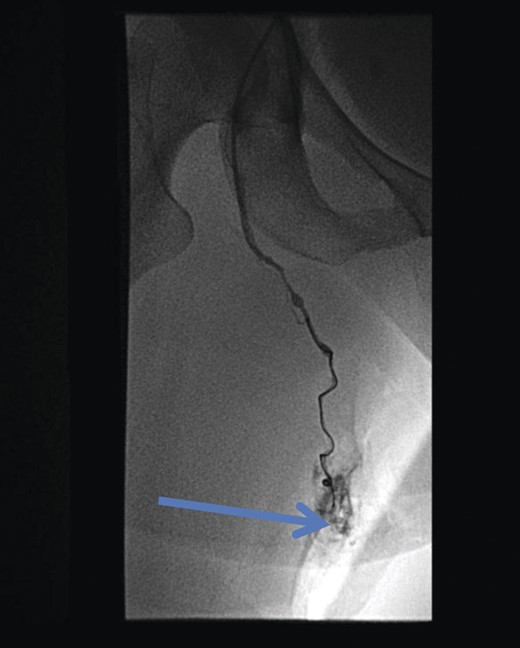

Pre-embolization fluoroscopy showing communication of thigh veins to vulval varices (blue arrow).